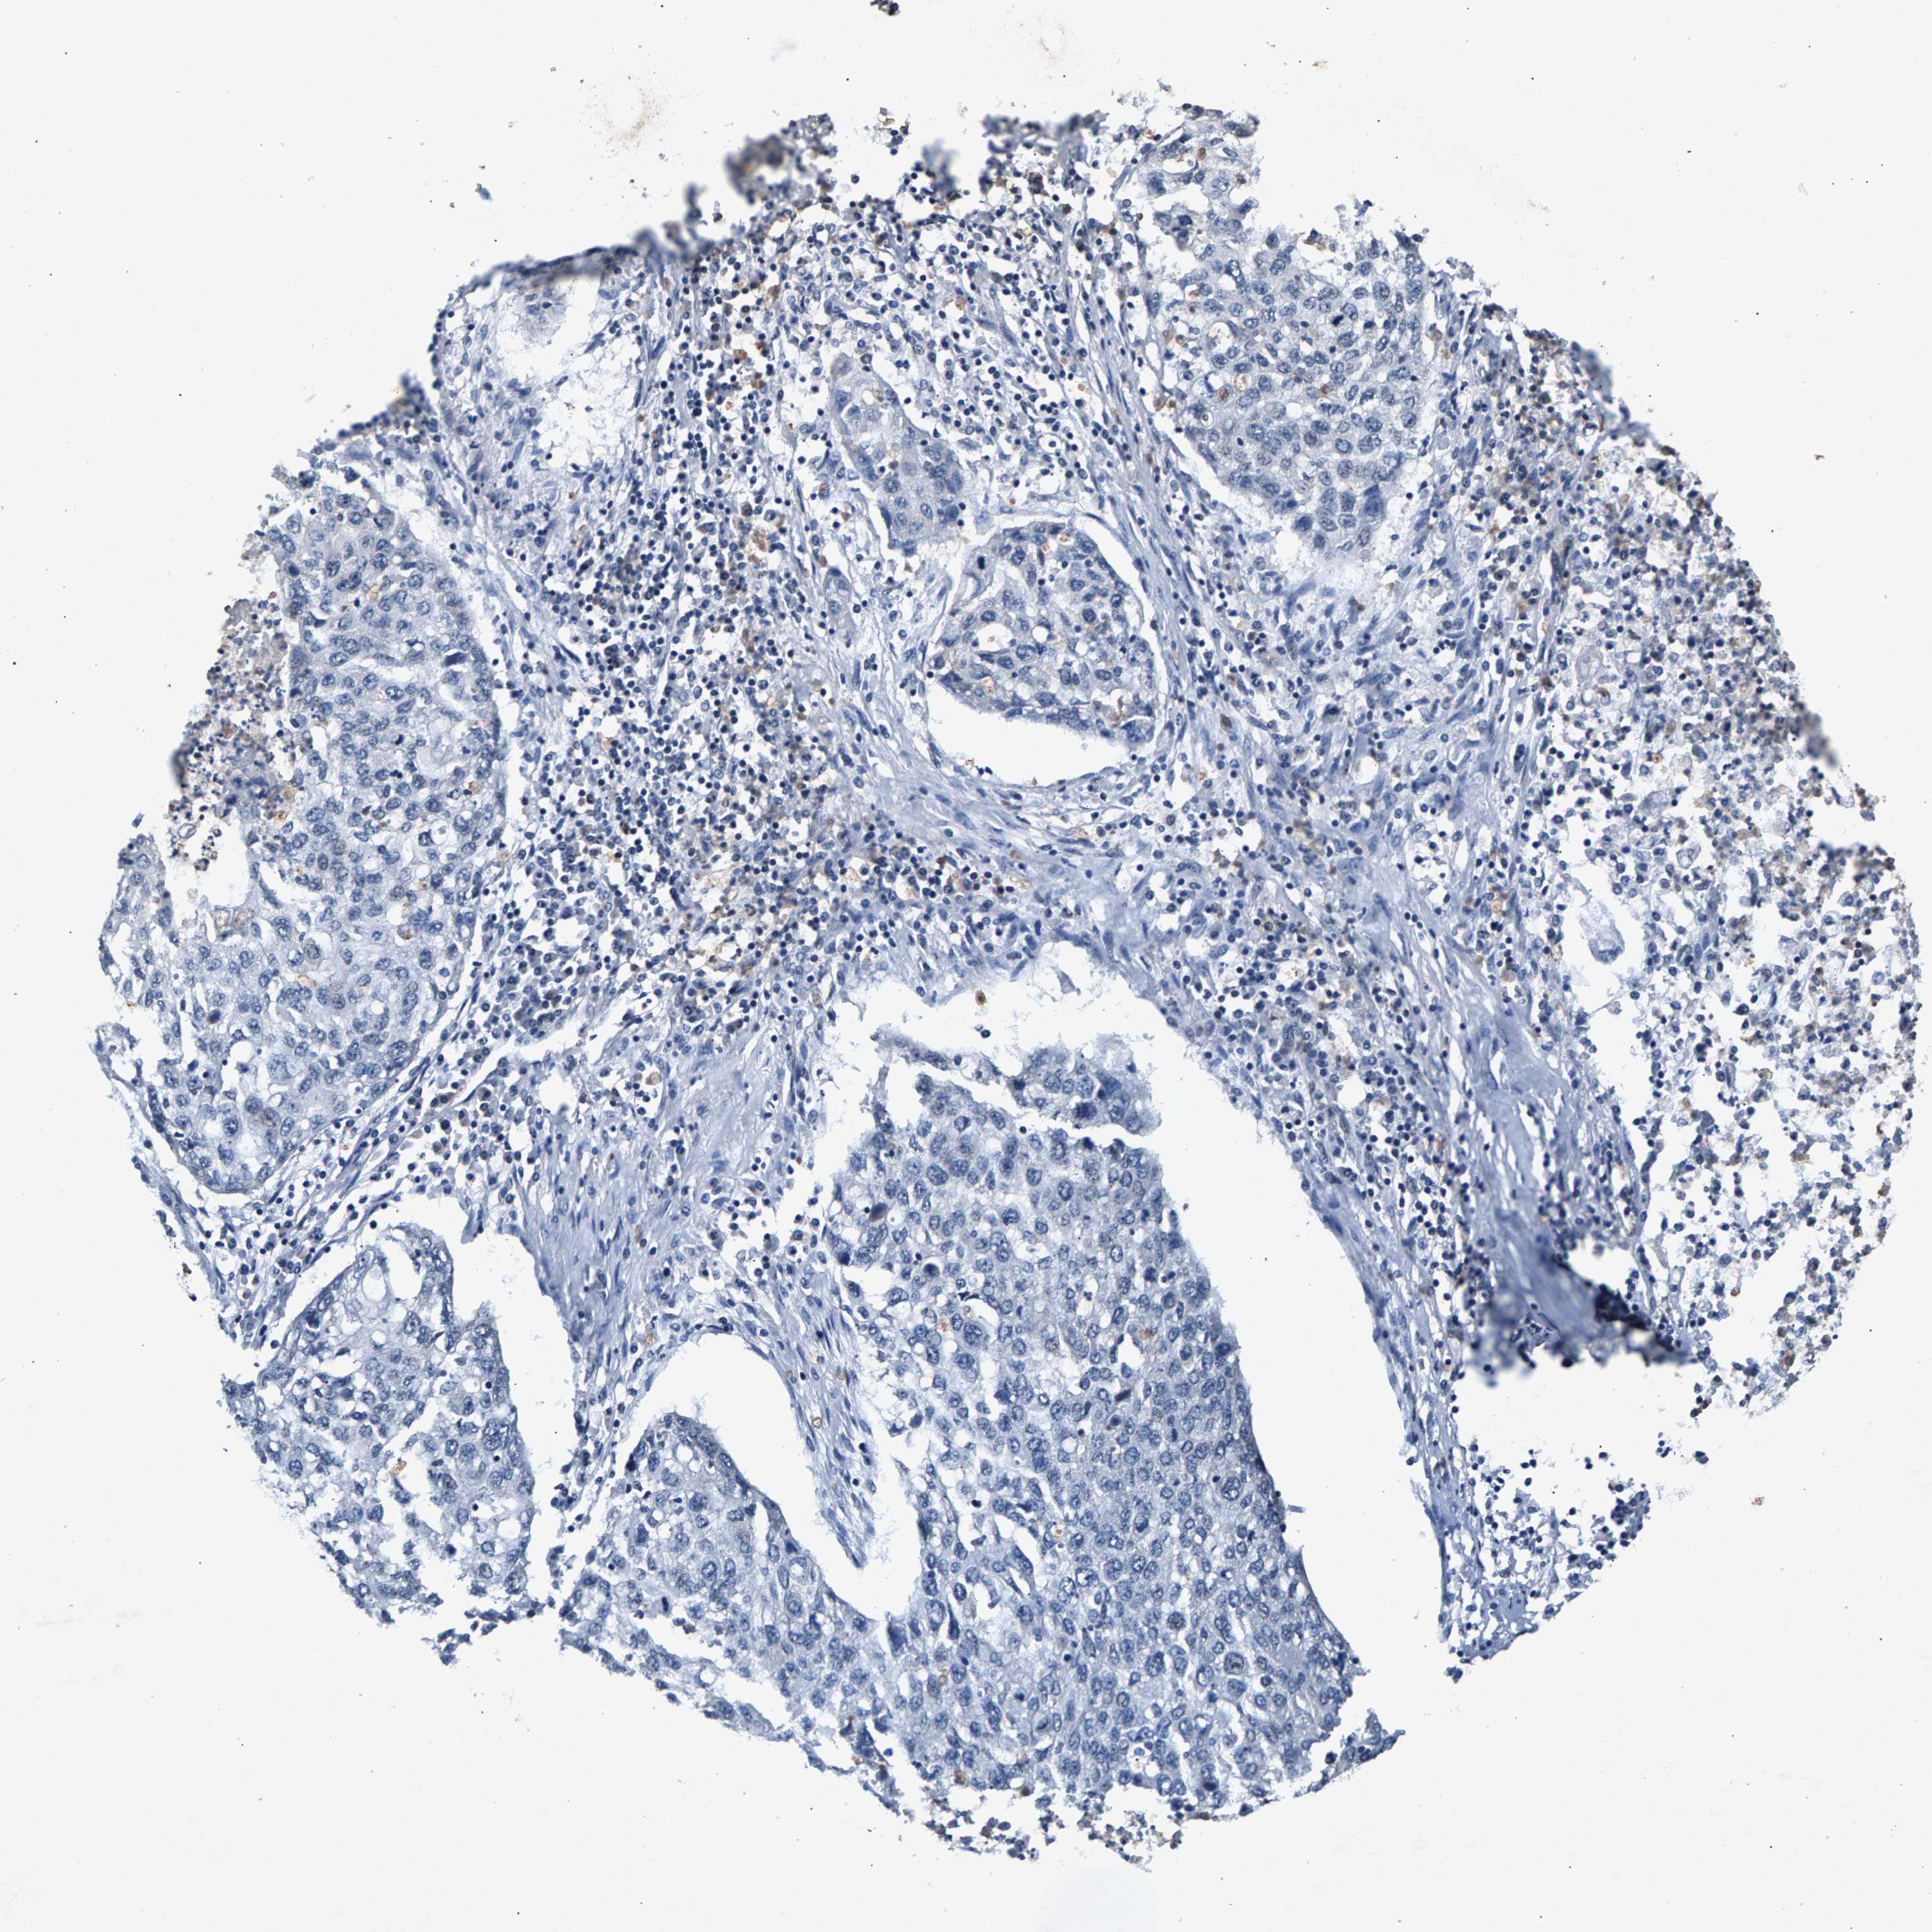

CANCER LUNG CANCER Show tissue menu

Lung cancer

Human cancer

Lung adenocarcinoma

Lung squamous cell carcinoma